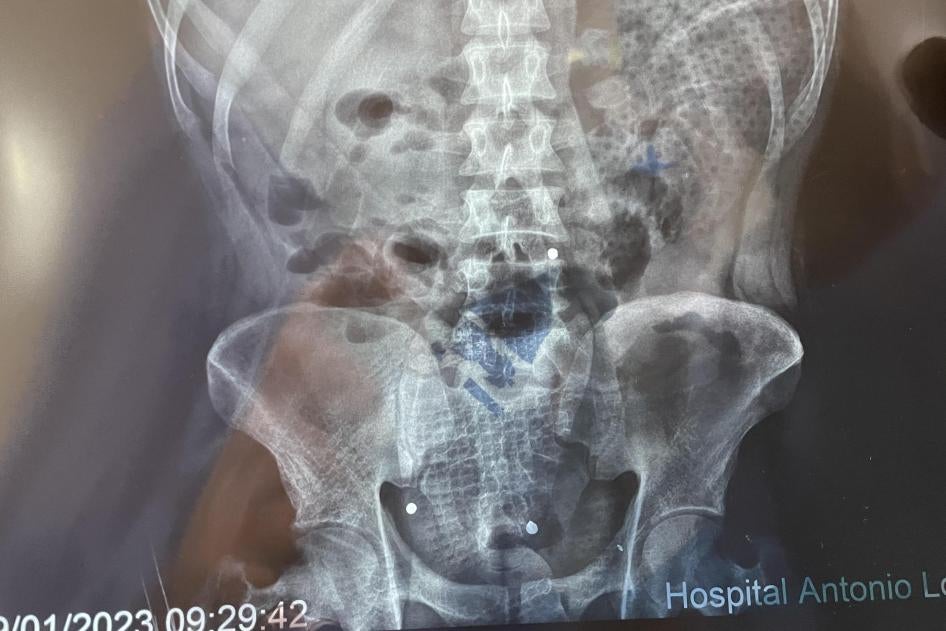

Pellets that police fired from shotguns caused injuries in January 2023 that killed at least five people in Juliaca, Arequipa, and Cusco. Victims were hit by multiple pellets, indicating they were shot at close range, as this type of projectile scatters with distance. In one case, CCTV footage verified by Human Rights Watch shows a police officer shooting at a young man from roughly seven meters away, as he fled. An X-ray showed about 30 pellets in his body. He died in March 2023. At least 71 people were injured by pellets, Ministry of Health data show.